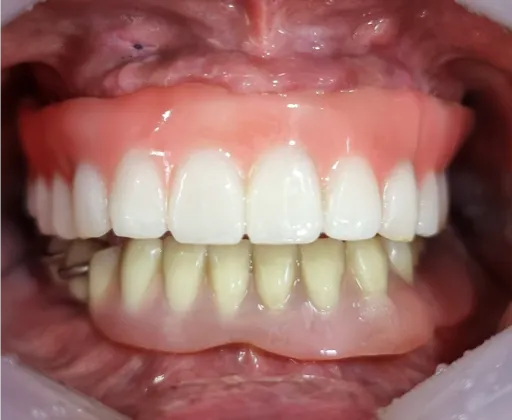

3D 모의시술로 발치 후 바로 임플란트 식립하고 임시 보철물 당일 장착하였습니다

당일 임시 보철물 장착 (2023.10.23)